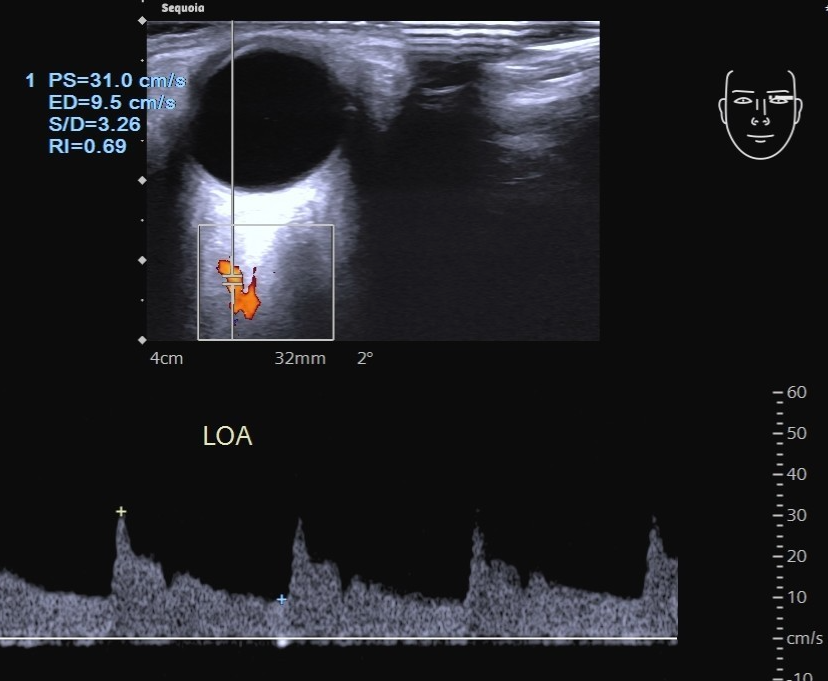

第 3 段眼动脉绕过视神经向前行走于视神经鼻侧,并分出其末支。频谱多普勒显示眼动脉为直角三角形,且呈三峰两谷型,峰速在 30 ~ 40cm/s(图 2 )。

图 2 眼动脉超声多普勒频谱

图片来源:作者提供